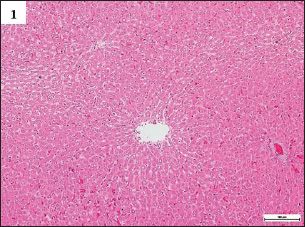

Fig. 1. Photomicrographs of H&E-stained livers in the sub-chronic trial at 10× magnification. The livers in Group A were normal, having sinusoidal capillaries and hepatocytes positioned regularly around the central vein.

In this study, the histological lesions present in the liver tissue samples examined and the findings of all the experiments were compiled. The findings showed that the liver slices extracted from Group A animals displayed a normal level, wherein the tissues showed the presence of normally placed hepatocytes that surrounded the central vein, in addition to general sinusoidal capillaries (Figs. 1 and 4) (Table 2). However, the liver tissue slices extracted from the animals in Group B displayed significant treatment-induced histopathological changes, which included vacuolation, degeneration, and necrosis of hepatocytes with the accumulation of inflammatory cells, especially mononuclear cells; also noted clear swelling of hepatocytes, or became like balloons. Some samples displayed histological changes related to capsular and advanced septal fibrosis. Further histopathological analysis revealed that the rabbits had hepatitis since the infiltration of inflammatory cells was noted in addition to their congestion (Figs. 2A–G and 5A–C) (Table 2). On the other hand, the analysis of the liver sections extracted from the Group C animals did not display any structural variations (Figs. 3A and B, 6A and B) (Table 2).